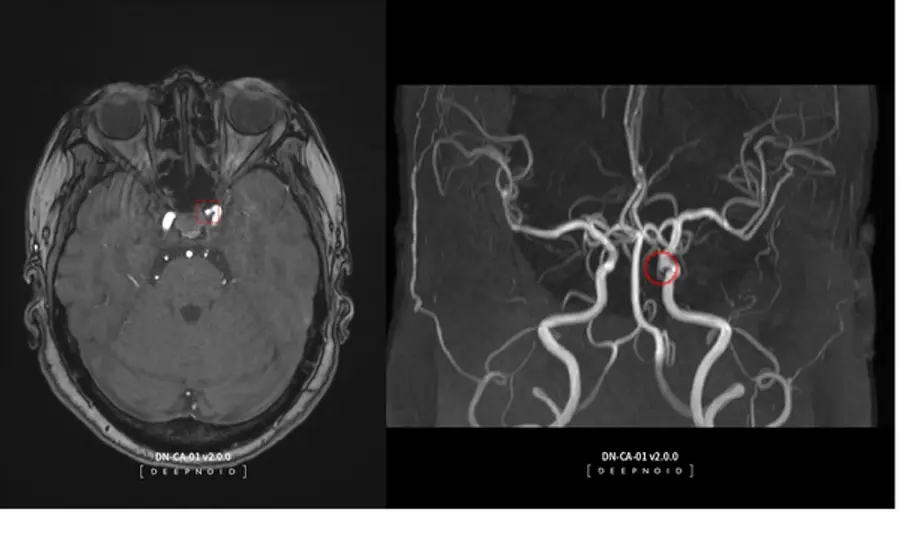

딥노이드는 2008년 설립된 국내 1세대 AI 개발 전문 업체로, 사업군은 크게 의료 AI와 산업 AI로 분류된다. 뇌동맥류 AI 영상 판독 솔루션인 딥뉴로(DEEP:NEURO)와 딥러닝 기반 머신비전 솔루션인 딥팩토리(DEEP:FACTORY)를 주력 제품으로 보유하고 있다.